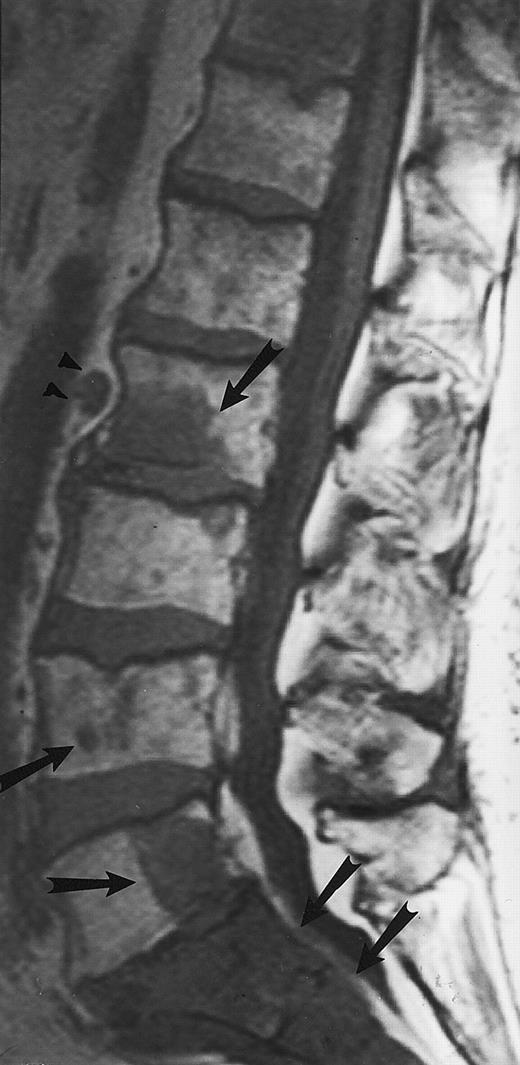

Normal appearance of spinal bone marrow in a 45-year-old woman: T1-weighted (500/11, TR/TE) (A) and T2-weighted, fat-suppressed fast spin echo (4000/96, TR/TE, ET 16) (B) sagittal MR images of the lumbar spine. Note increased signal of the vertebral bodies, relative to the intervertebral discs in (A) and increased deposition of fatty marrow around the basivertebral veins (arrowheads). On the T2-weighted image, normal intervertebral discs are brighter than the vertebral bodies; low signal in the L4-L5 and L5-S1 discs is due to degenerative changes (arrows).